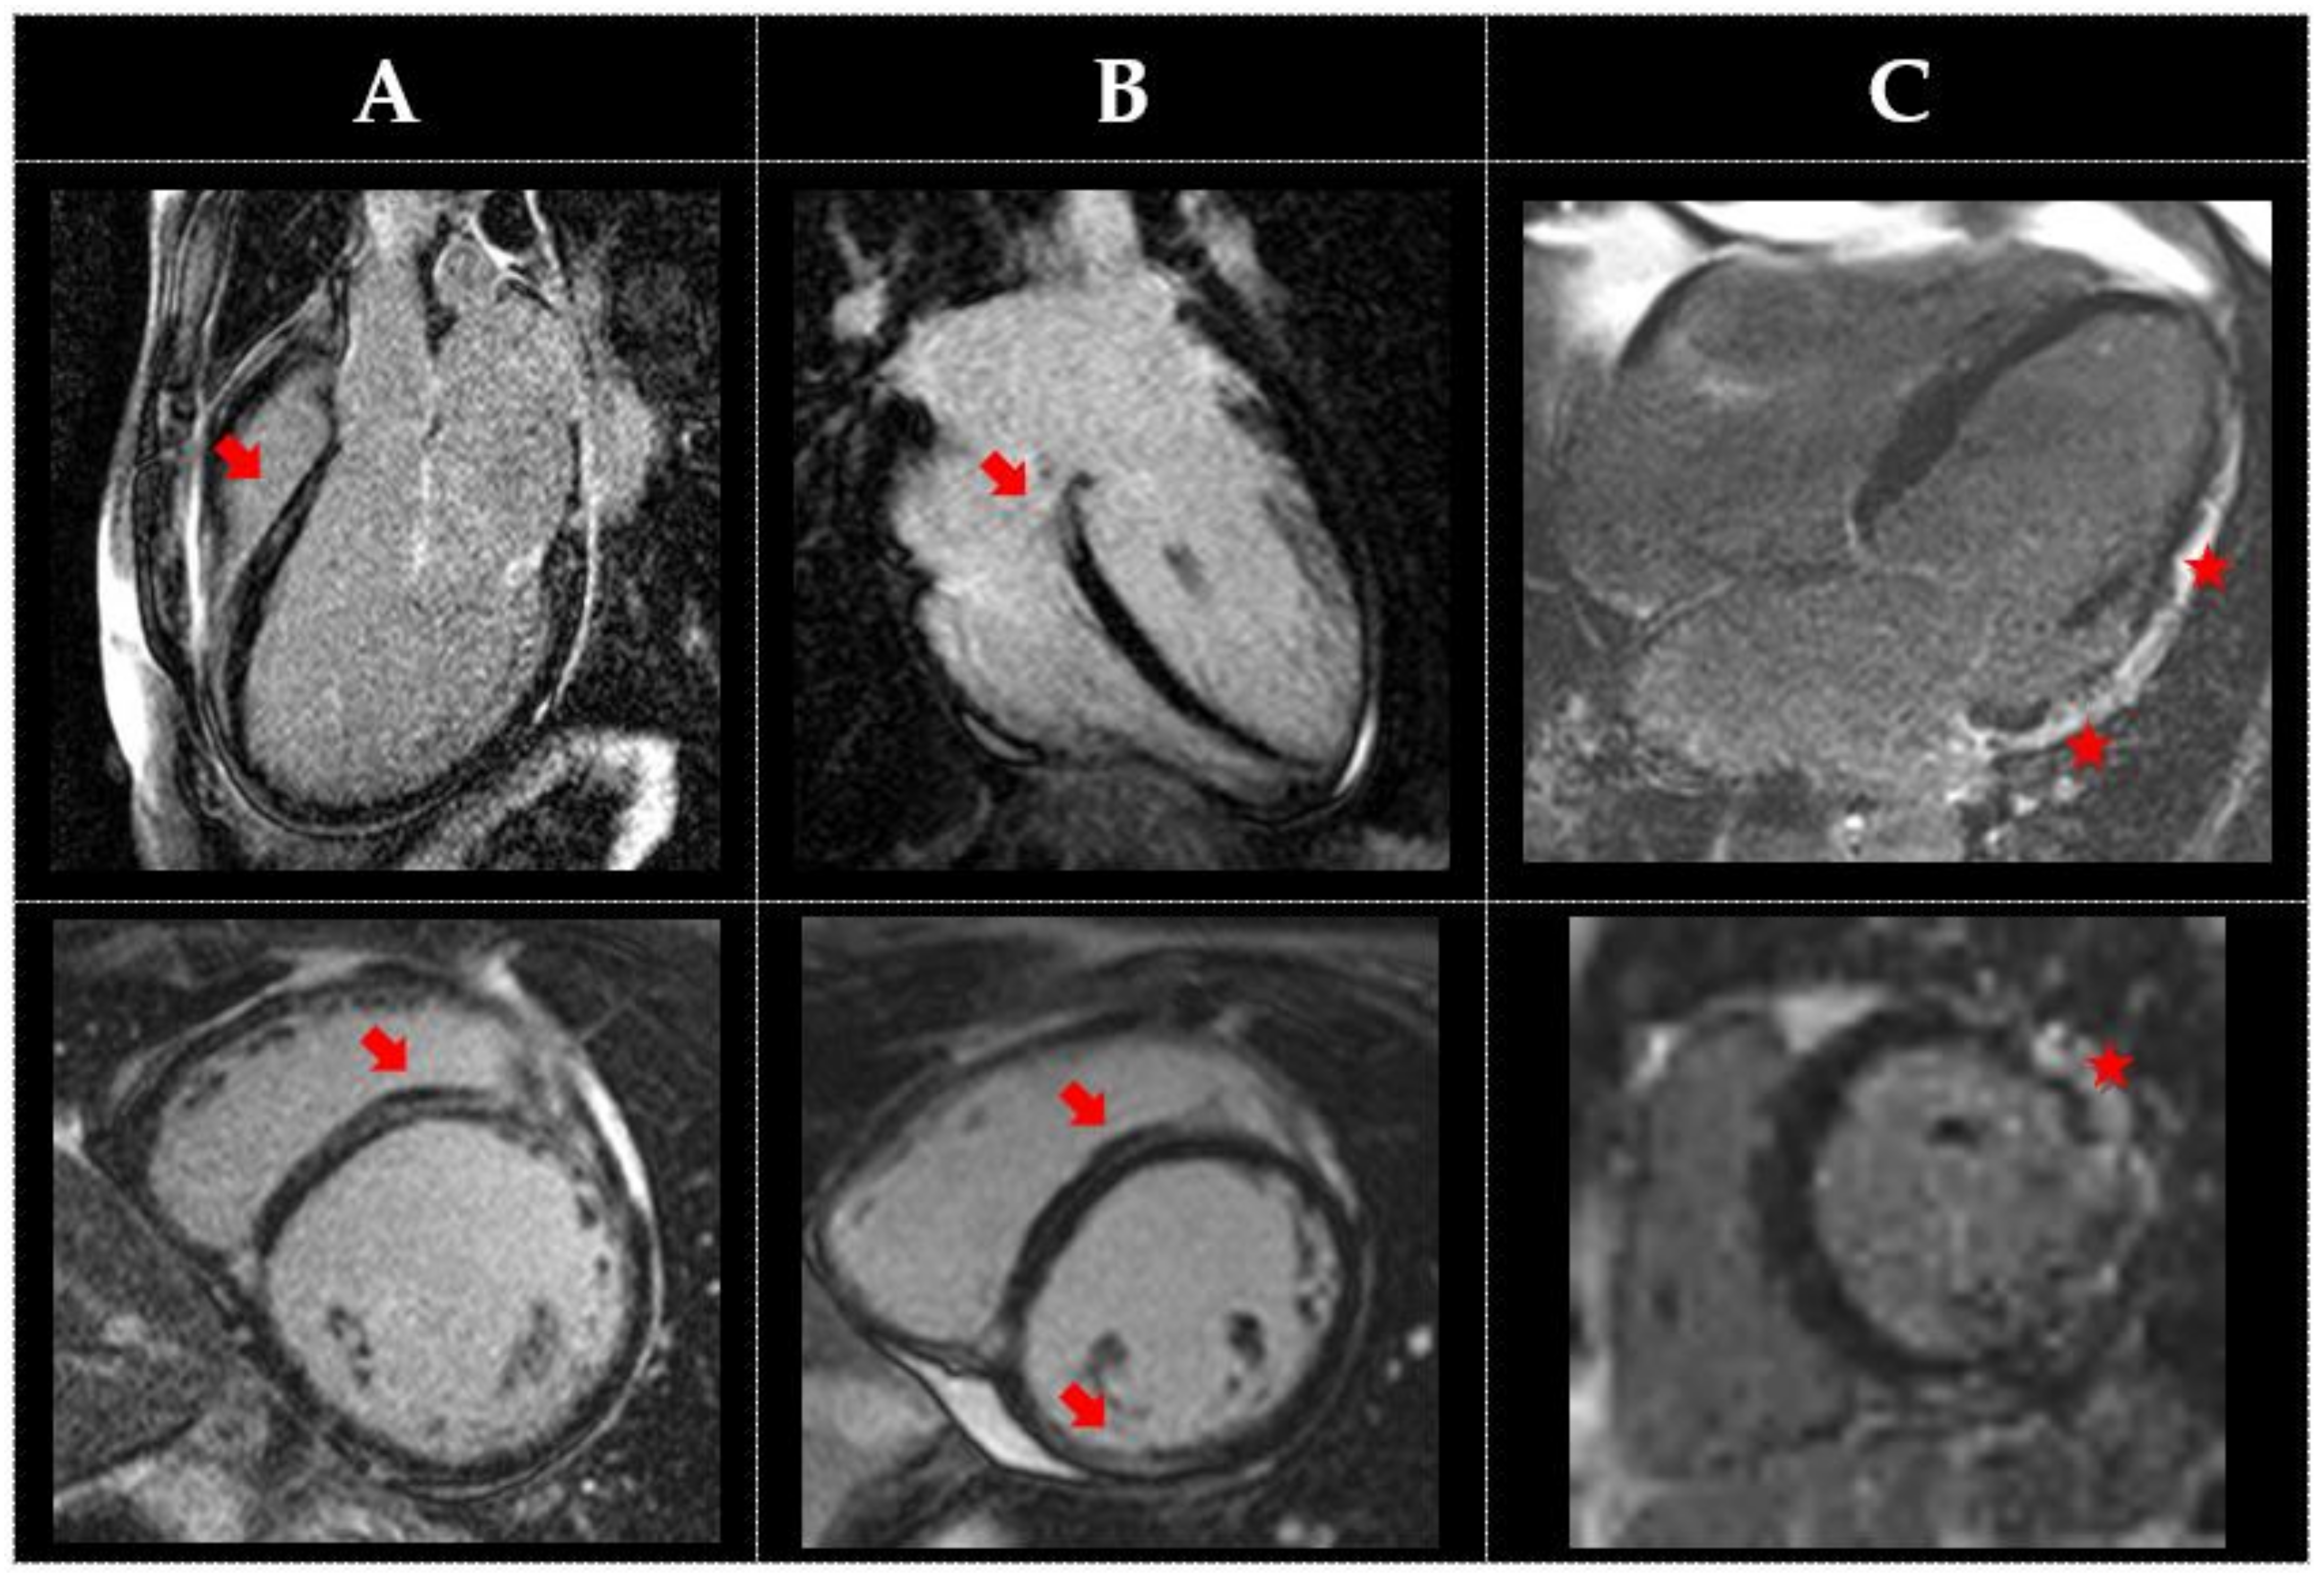

| Lamin | Recommended commencing 10–12 years by ECG and Echo Autosomal dominant | Young age onset and progression | Conduction or depolarization abnormalities, such as IVCD/BBB/ Early abnormalities in strain or diastolic function | Arterial and venous thromboembolism | Isolated LV dilation or dysfunction; marked dilation unusual Wall thinning not present RWMAs (basal) in Lamin A/C HNDCM to DCM progress | Prominent right ventricular epicardial fat Early increase in ECV LGE shows basal to mid septal, mid-myocardial fibrosis (extensive fibrosis only late in disease) | Increased arrhythmias and both AV and SA nodal conduction disease |

| Dystrophin (DMD and BMD) | Cardiac screening recommended in mutation carrier females along with affected males Consider CMR in screening alongside ECG and echo X linked | Childhood onset, progression from HNDCM to typical DCM. BMD has an earlier and more severe disease course than DMD | Increased right precordial ECG R-to-S ratio Deep Q waves in the lateral leads Early abnormalities in strain | Typical skeletal muscle weakness and disability in affected May be none in carriers | Wall thinning and RWMAs lateral wall, inferior, or septum Early increased ECV, while still normal function DCM or HCM phenotype | Mid-wall or subepicardial fibrosis in hypokinetic segments (inferolateral) in early disease (sometimes with preserved LV function) Fibrosis becomes extensive or transmural in advanced stages | Conduction abnormalities and tachyarrhythmias (both SVT and VT) Early onset in severe forms |